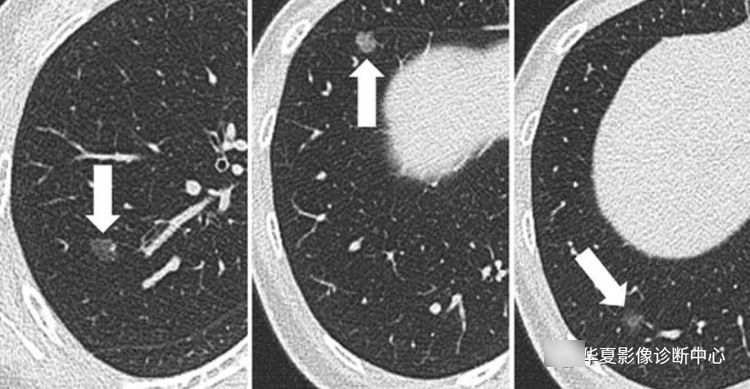

5、多发纯GGO,至少一个病变大于5 mm,但没有特别突出的病灶,建议3月后复查,且长期随诊,至少随诊3年。

6、有突出病灶的多发GGO,主要病变需进一步处理。首次3月后复查,病灶若持续存在,建议对较大病灶给予更积极的处理,尤其是病灶内的实性成分大于5 mm者。术式推荐胸腔镜楔形手术或肺段切除。术后病人每年随诊,至少持续3年。对于肺内的磨玻璃密度结节,目前最重要和最需要解决的问题是可能存在过度治疗。